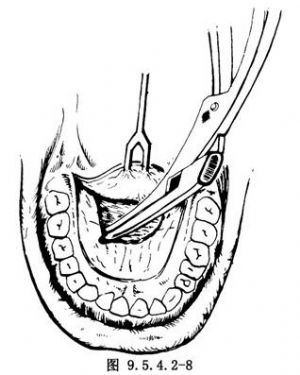

(3)分離硬齶鼻腔面黏骨膜,咬除硬齶骨質:在硬齶後緣處用直角骨膜剝離器將硬齶鼻腔面黏骨膜分離後,改由普通剝離器繼續向鼻腔方向分離,分離深度根據腫瘤向鼻腔擴展程度而定,然後用咬骨鉗咬除切口以內的硬齶骨質(圖9.5.4.2-8)。